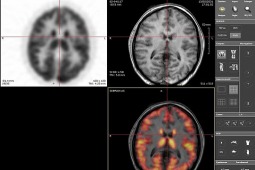

Dotychczas najlepszą metodą diagnozowania nowotworu W Polsce była tomografia pozytonowa z wykorzystaniem tomografii komputerowej. Bydgoskie Centrum Onkologii posiada już doskonalszy sprzęt - tomografię komputerową z rezonansem magnetycznym.